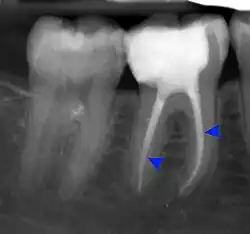

Decay (green) with apical abscess (blue) -

Gutta-percha point indicating abscess origin